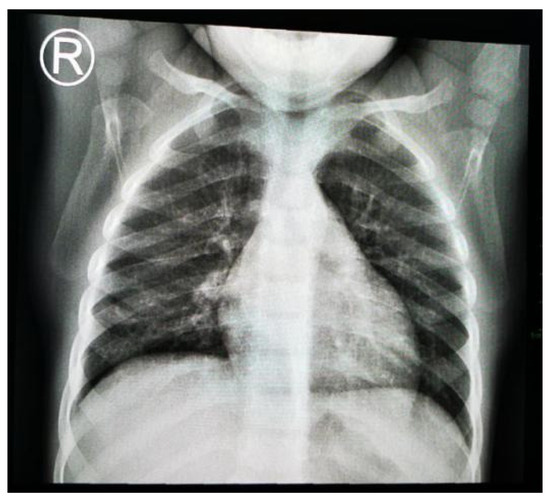

1.9.2. Case 2